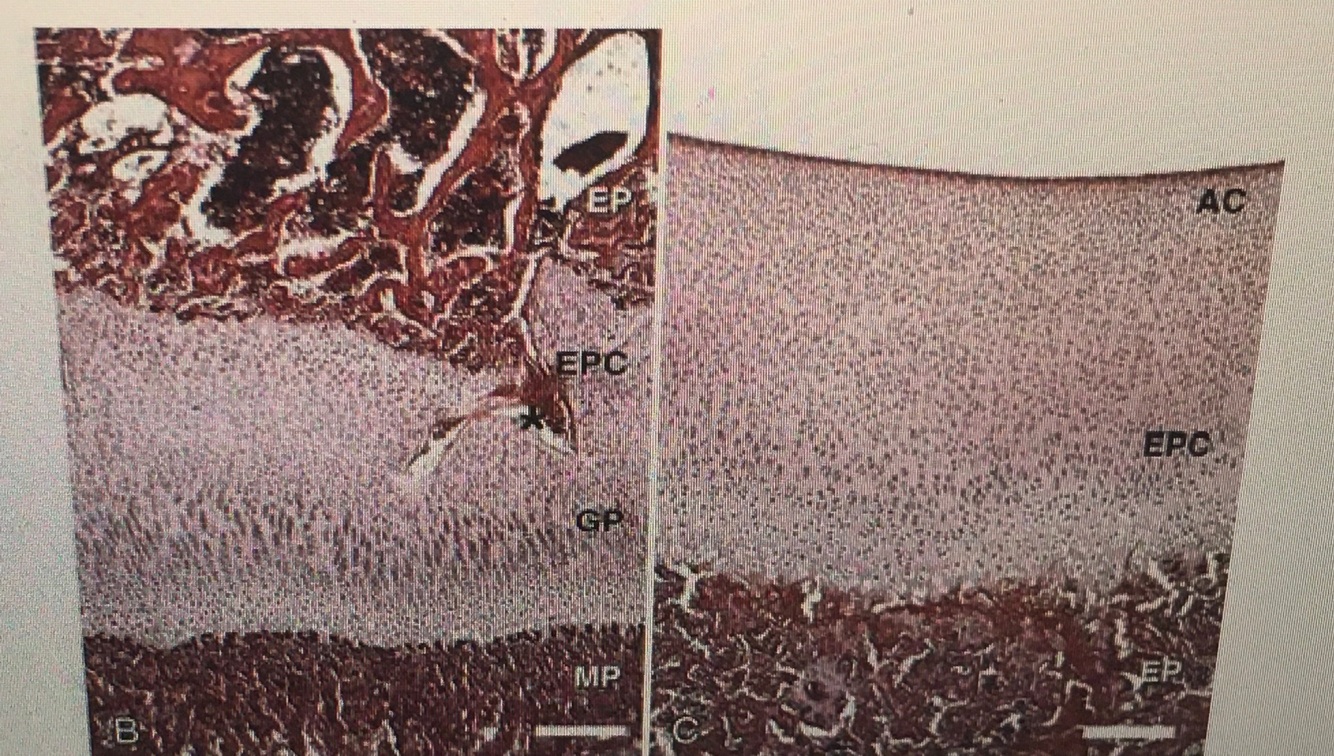

• What is being shown in these images?

• The first image shows the growth plate and it’s relationship to the epiphysis

• The second image shows the epiphysis in relation to the developing articular cartilage